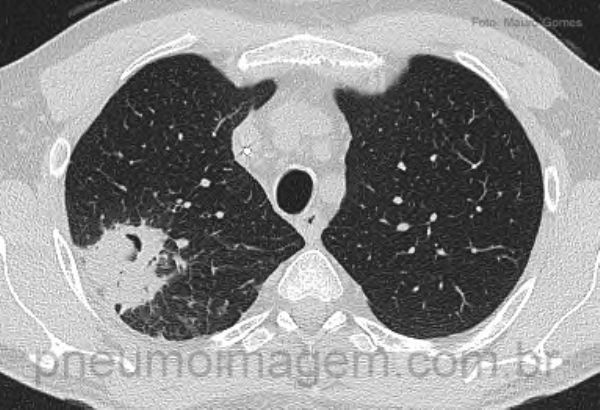

As lesões iniciais incluem nódulos (seta vermelha) circundados por áreas em vidro fosco (seta amarela), configurando o sinal do halo. O sinal do halo reflete hemorragia como resultado da trombose e necrose provocada pela presença das hifas dentro dos capilares.

CT findings in IA are variable according to the host. The early lesions include nodules (red arrow) surrounded by areas of ground glass (yellow arrow), setting the halo sign. The halo signal means hemorrhage as a result of thrombosis and necrosis caused by the presence of hyphae inside the capillaries.